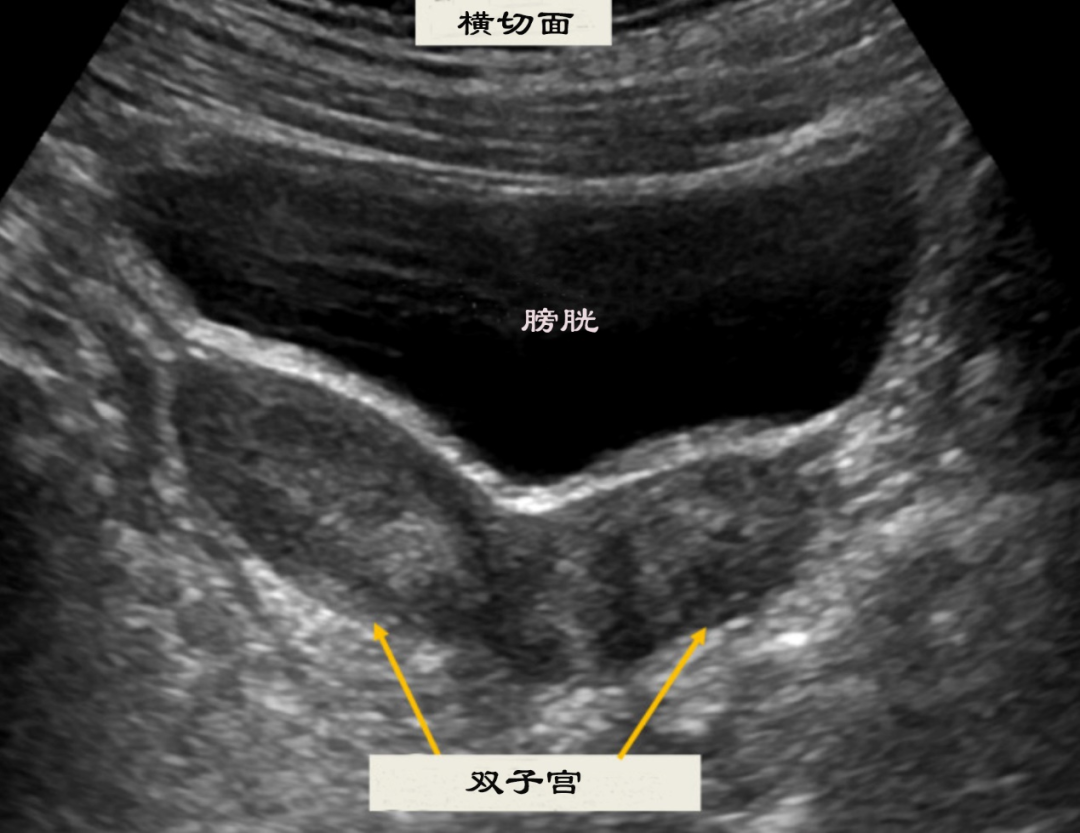

① 经腹部超声:从腹部观察子宫整体形态、数目及与周围器官关系。

② 经阴道超声:分辨率更高,可清晰显示子宫内腔、宫颈及阴道情况,便于发现双宫腔、双宫颈或纵行阴道隔。

超声典型表现包括:两个不相通的宫腔、分离的子宫体、明显的子宫底切迹以及可能存在的双宫颈等。